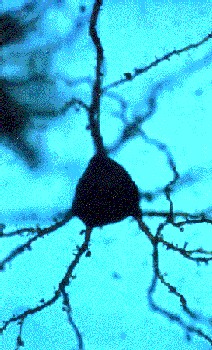

La plasticidad sináptica es la que permite que las conexiones neuronales no sean rígidas, sino que adapten sus terminaciones en respuesta al flujo de información existente en el sistema nervioso central. Cada una de las neuronas de nuestro cerebro posee la capacidad de modificar sus propiedades, así como los patrones de conexión entre ellas, gracias a la plasticidad sináptica. De esta manera, es posible la adaptación del organismo al medio. Dicha plasticidad puede ser o bien ambiental o bien genética.

La formación y la conservación de los recuerdos en el cerebro se produce gracias a la extraordinaria capacidad plástica del sistema nervioso: cambios perdurables en la fuerza de las sinapsis, que son las conexiones entre neuronas, así como una remodelación funcional y estructural de las redes neuronales activadas durante el aprendizaje, son los procedimientos que sigue el cerebro al aprender.